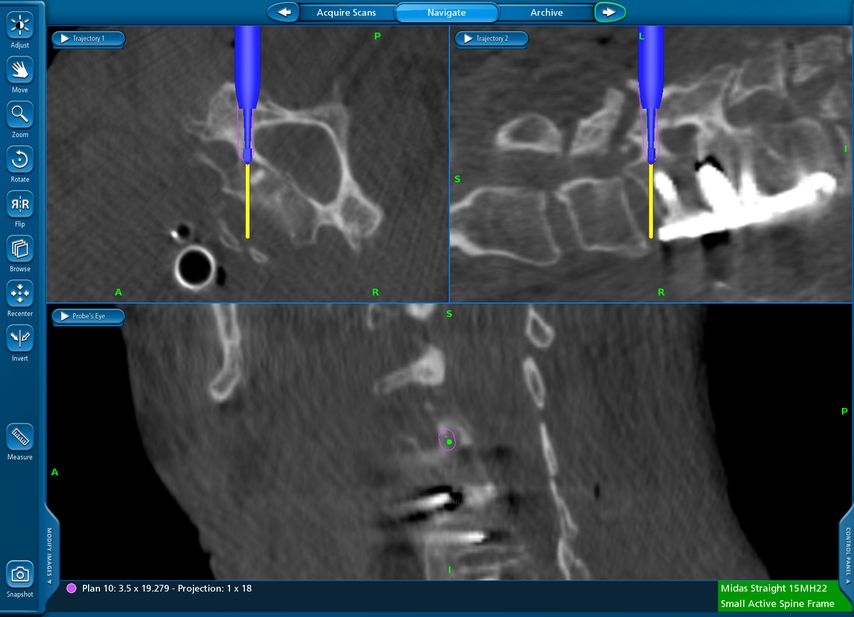

TLIF über Mittellinienzugang mit Schrauben in „cortical bone trajectory“. Bei der 63-jährigen Patientin bestand eine degenerative Spondylolisthese Meyerding Grad I mit Facettengelenkszysten und Wirbelkanalstenose (Abb. 8). Klinisch bestanden Lumboischialgien mit Ausstrahlung dem Dermatom L5 bds. entsprechend. Es wurde ein Mittellinienzugang durchgeführt und zuerst wurden navigierte Schrauben in „cortical bone trajectory“ platziert (Abb. 9). Anschließend erfolgten eine Facettektomie L4/5 links und eine Dekompression des Wirbelkanals. Abbildung 10 zeigt, dass der Hautschnitt aufgrund der mittelliniennahen Schraubenköpfe klein gehalten werden kann. Klinisch wurden die lumbalen Schmerzen wie ausstrahlende Beschwerden 1 Jahr postoperativ annähernd vollständig behoben, die korrespondierende Röntgenkontrolle ist in Abbildung 11 dargestellt.

Lumbale Pedikelschrauben in „cortical bone trajectory“ sind eine weitere gute Einsatzmöglichkeit für die Navigation. Im Gegensatz zu konventionellen Pedikelschrauben haben diese Schrauben ihren „entry point“ medial und kaudal am Pedikel, der Zielpunkt liegt lateral und kranial im Wirbelkörper. Ein wesentlicher Vorteil dieser Schraubentrajektorie besteht – neben der verbesserten Verankerung, insbesondere bei osteoporotischem Knochen – darin, dass der mittelliniennahe Eintrittspunkt nur ein sehr begrenztes Abpräparieren der autochthonen Rückenmuskulatur erfordert und der Hautschnitt klein gehalten werden kann.10,11 Da die Trajektorie dieser Schrauben herausfordernd ist, wurde diese Schraubentrajektorie hauptsächlich für den Einsatz kombiniert mit Robotik vorgeschlagen, ist jedoch auch mittels Navigation gut umsetzbar.